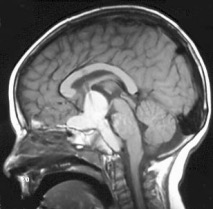

la tumeur se développe à partir de la tige pituitaire, qui peut très rarement être préservée lors de la résection. Elle se développe donc dans la région supra-sellaire, soit en dessous du diaphragme sellaire (forme sous-diaphragmatique), soit au-dessus (forme supra-diaphragmatique), soit de part et d’autre.

les formes supra-diaphragmatiques sont en contact plus ou moins étroit avec les voies visuelles et l’hypothalamus, pouvant même infiltrer ce dernier rendant l’exérèse illusoire et dangereuse. l’extension intraventriculaire, souvent kystique, peut réaliser un blocage ventriculaire avec hydrocéphalie aiguë. les formes sous-diaphragmatiques au contraire se clivent en général bien des structures nerveuses, mais elles infiltrent souvent le sinus caverneux et l’exérèse peut alors être incomplète.

l’imagerie

il s’agit d’un tumeur supra-sellaire souvent calcifiée et kystique

l’imagerie étudie ses rapports avec l’hypothalamus, les voies visuelles, les structures du sinus caverneux.